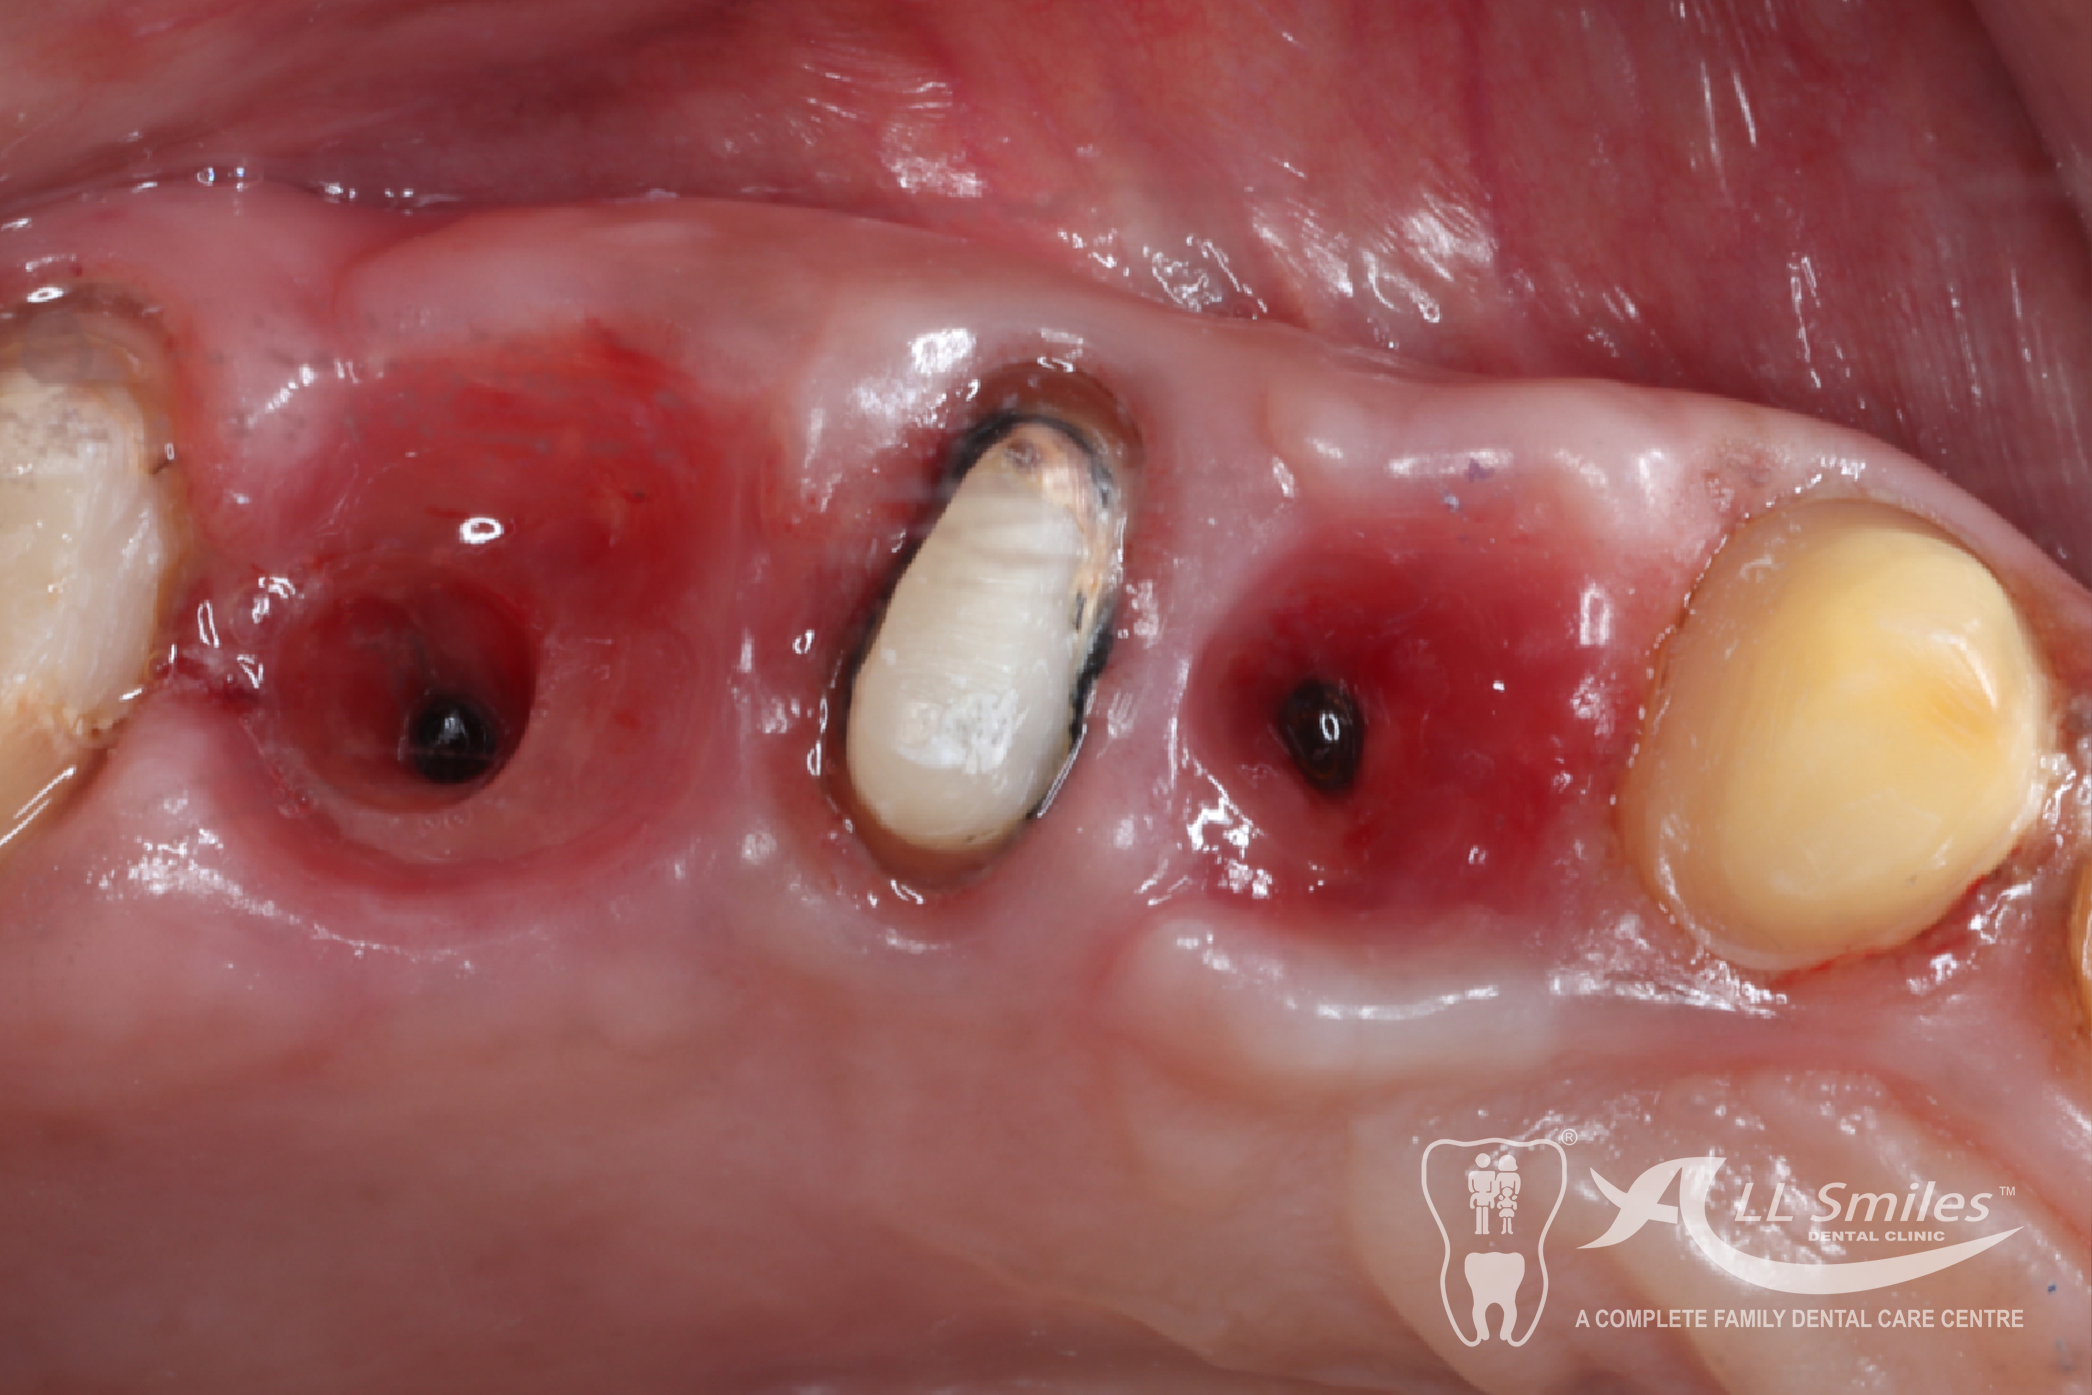

Root Canal Gallery